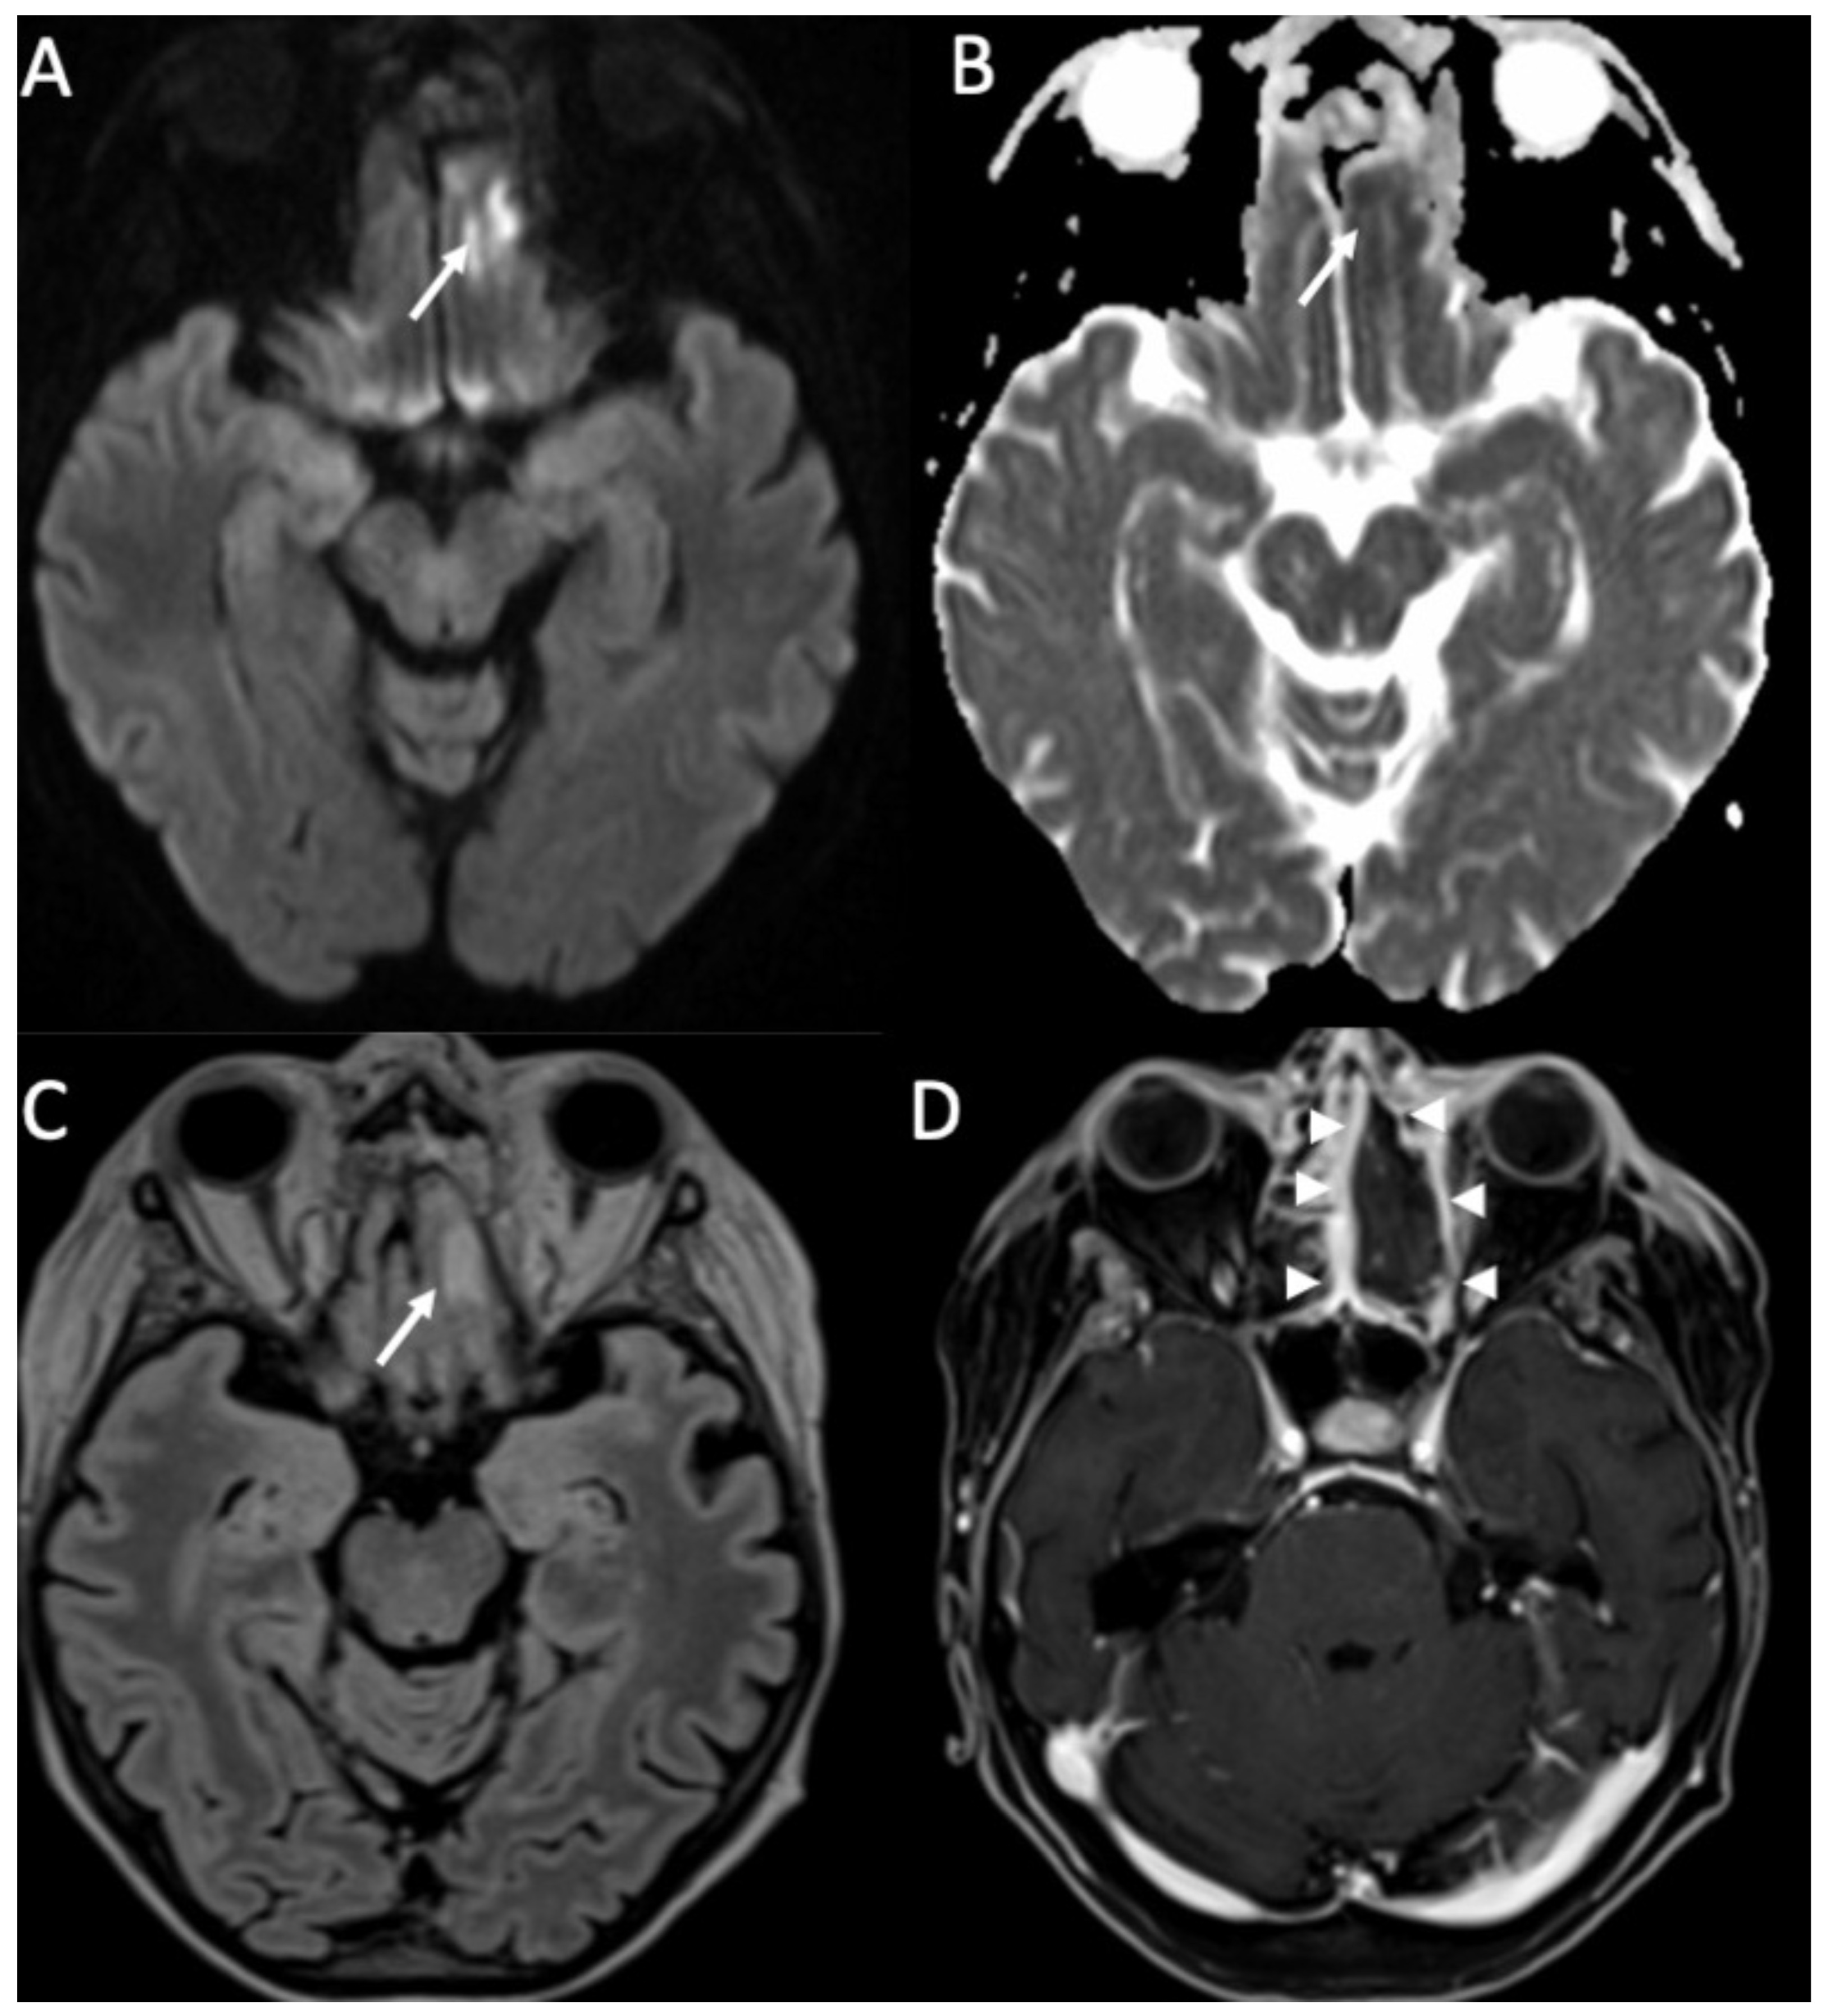

Concomitant granulomas may be seen, and they are called tuberculomas and they can be noncaseating or caseating [9]. Noncaseating tuberculomas on CT are iso to hypodense, whereas on MRI, they are hypointense on T1 and T2-weighted sequences, with homogeneous contrast enhancement (Figure 9). On the other hand, caseating tuberculomas are usually hyperintense on T2 images, with rim enhancement due to central liquefaction.

Figure 9.

Axial FLAIR (A), T2 (B), and enhanced T1 (C) shows a tuberculoma in the right frontal region, which is hypointense in FLAIR and T2, and has intense contrast enhancement (arrows in A–C). Note also the surrounding vasogenic edema (arrowheads in A,B).

Miliary tuberculomas are frequently seen in patients with tuberculous meningitis [9]. It is characterized by the presence of multiple tiny lesions (with a diameter ranging from 2 to 5 millimeters), whose signal is hypointense on T2, show homogeneous contrast enhancement, and are frequently surrounded by vasogenic edema (Figure 10).

Figure 10.

Axial FLAIR (A,B) and enhanced T1 (C,D) depict multiple tiny foci of enhancement, some of which have a ring appearance (arrows in C,D) in a patient with miliary tuberculosis. They are surrounded by vasogenic edema (arrowheads in A,B).

Aspergillus is commonly present in soil and water, and Aspergillus fumigatus is the most commonly involved in neuroinfection, which is seen in patients with immunodepression [43]. Aspergillus may cause cerebritis (Figure 12), which can evolve into abscesses. They are characteristically surrounded by a hypointense rim in T2 and gradient-echo images due to hemorrhage and hyphae [10]. They also show restricted diffusion peripherally. Vascular invasion is common, with vasculitis, infarction, mycotic aneurysms, and intracranial hemorrhage [44].

Figure 12.

Axial DWI (A), ADC (B), FLAIR (C), and enhanced T1 with fat-suppression depict an area of cerebritis in the left rectus gyrus (arrows in A–C), which shows restricted diffusion and hyperintensity on FLAIR (arrow in C). Also note the sinusitis in the left anterior ethmoidal cells, with necrosis of the mucosa (arrowheads in D).